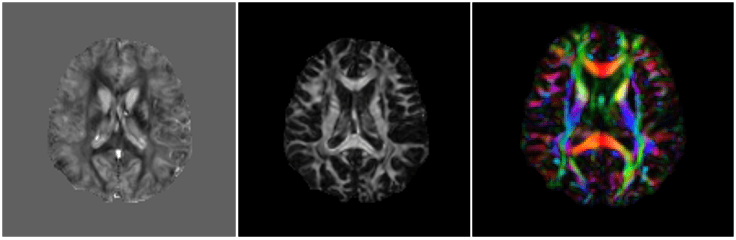

Susceptibility Tensor Imaging

Mean

Anisotropy

PEV

Time-consuming data acquisition

Dipole Convolution

Dipole Inversion

Inverse Problem in STI

- \(A\): depends on number of orientations, angles

- Number of orientations < 6: ill-posed

Phase measurements at different angles